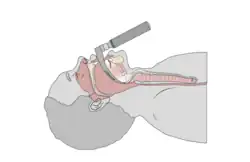

Tracheal Intubation

Tracheal intubation involves the placement of a tube, known as an endotracheal tube, into the mouth or nose. Intubation first begins with the use of anesthesia medications, usually delivered through an IV, to place the patient to sleep. Next, extra oxygen is administered to the patient through a face mask. Once the patient is asleep, an anesthesia provider will tilt the patient's head back and insert a viewing device, also known as a laryngoscope, into the patient's mouth. The laryngoscope is accompanied by a dull blade to help move other oral structures, such as the tongue, out of the way. Once the anesthesia provider identifies the epiglottis, which covers the larynx, the epiglottis is manually lifted using the laryngoscope.[8] The endotracheal tube is inserted through the larynx past the vocal cords and secured by inflating a small balloon at the end of the endotracheal tube. Once secured, the laryngoscope is removed. The tube is then secured at the mouth, often using tape or with a strap that wraps around the patient's head. Finally, correct placement is verified by listening to both lungs for breath sounds.[1]